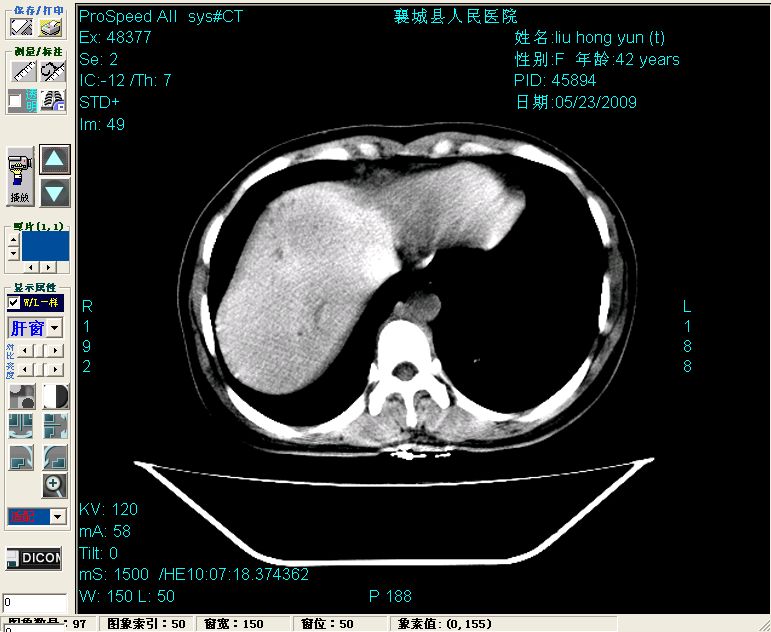

增强:

增强动脉期前述低密度区轻度早其强化,门脉期强化程度显著增高,延期扫描强化程度下降,但仍为相对高密度影

胰头部见结节状高密度影,其前方略可分辨扩强胆部管,平扫到增强始终有,但现在尚难与胃肠造影剂鉴别.